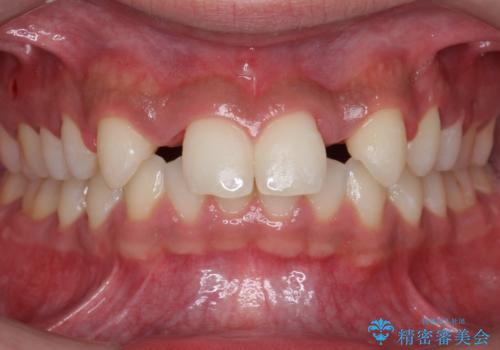

バラバラに位置している前歯の位置を矯正治療で修正してからブリッジを装着しています。

矯正治療によって事前に歯の位置を修正しているため、ダミーの歯の大きさも調整し、自然な仕上がりにしました。また、犬歯のねじれを治してから削っているため、神経をとらずに歯の形を整えることができました。